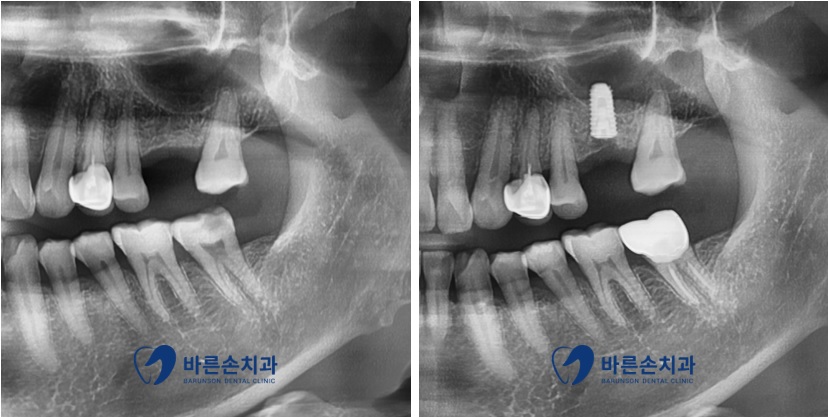

정확한 손상 범위를 알기 위해 엑스레이 촬영을 진행하였습니다

엑스레이 촬영을 해본 결과

치아의 신경관 가까이까지 충치가 진행되어 있는 것을 알 수 있습니다

신경 치료를 진행하기로 하였습니다ㅜㅜ

몇 회에 걸쳐 신경치료를 완료 하였습니다.

크라운 치료까지 치료 완료 후 엑스레이 사진입니다

치료까지 잘 끝난 것을 확인할 수 있습니다

더불어

위에 임플란트 식립이 잘 된 모습 또한 보이네요^^